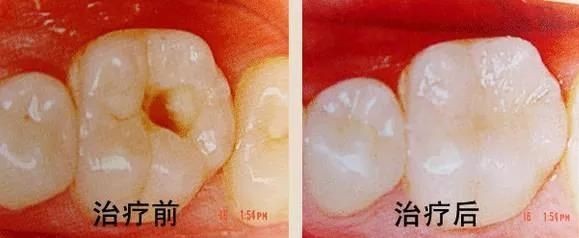

六、龋齿的治疗

银汞合金充填术

对已形成实质性缺损的牙齿,充填术是目前成效较好的方法。